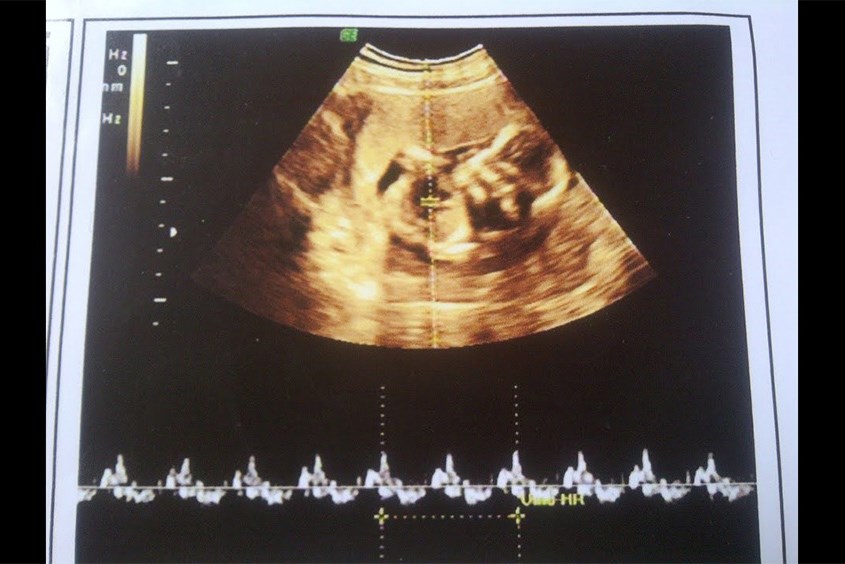

Thai nhỏ là thai dưới 7 tuần tuổi, kích thước của thai nhi lúc này rất nhỏ nên mẹ vẫn chưa cảm nhận được sự thay đổi nào, bên cạnh đó thai còn nhỏ nên bộ phận sinh dục chưa phát triển đầy đủ nên chưa xác định được giới tính của trẻ.

Hút thai chân không là một trong những phương pháp an toàn nhất hiện nay với hiệu quả lên đến 98%. Phương pháp này được thực hiện bằng các dụng cụ y tế chuyên dụng như ống hút dùng một lần được đưa vào trong tử cung để hút thai ra ngoài. Phương pháp này được dùng với những trường hợp thai nhi dưới 7 tuần tuổi.